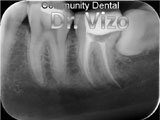

Clinical Work Photos

What We Do

Dental Services